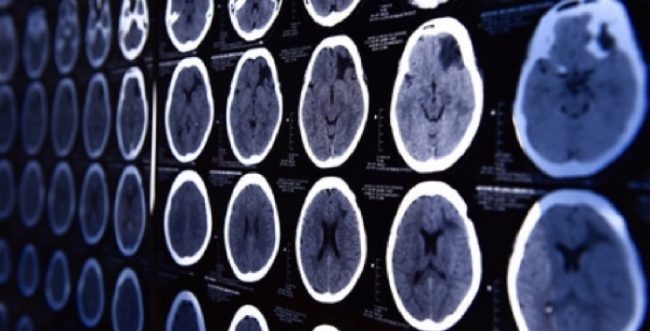

Hirntumor mit Neuro-Navi operieren (Köln/Bonn)

Im Diakonie Klinikum Siegen, Raum Köln-Bonn, profitieren Patienten mit Hirntumor von neuester Technik RAUM KÖLN/BONN. Die Diagnose Hirntumor ist für Patienten und Angehörige eine Situation größter Belastung. Umso wichtiger ist es für Betroffene zu wissen, dass sie die für sie bestmögliche Behandlung erhalten können. Die Neurochirurgie im Klinikum Jung-Stilling in Siegen hat jetzt mit einer…